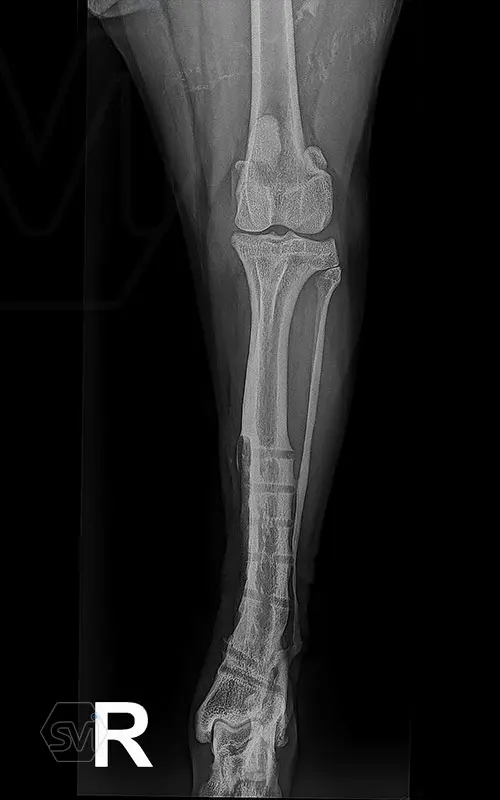

Multifunctional symmetrical long polyaxial locking plate - designed for the treatment of fractures close to joints

A special member of the polyaxial locking plate family is the multifunctional long plate, which is an extended version of the well-known symmetrical TPLO plate, with a 5-3 hole distribution. The plate also received a DCP hole to be able to create compression, and there is a mini-hole on the head end to facilitate the placement of the temporarily used K-nail. The burrs on the side facing the bone surface are intended to reduce the contact surface between the plate and the bone (limited contact).

The plate is a member of the large polyaxial locking family, suitable for 2.7-3.5-4.0 mm screws. We recommend it for fixaton of fractures close to joints, wedge osteotomies with axis correction (closing and opening), or for CWTO operations.